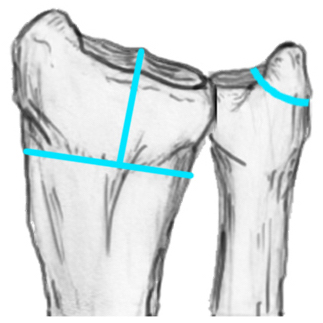

Distal Radius Angles

- radial volar tilt 11°

- radial inclination  22°

- radius is 11 mm longer than ulna

- ulna variance 2mm positive on average

Distal Radius NormalNormal Radial InclinationNormal Radial Length